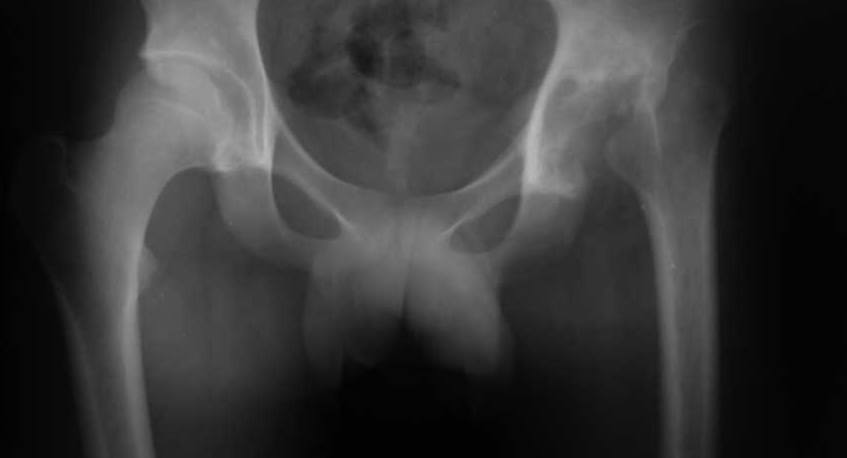

Ув. коллеги. пациент 19 лет, 4 мес назад перене гнойный коксит с затеками и т.д, 3 мес назад - резекция головки, санирование очага.

Выполнять эндопротезирование Вашему пациенту, с моей точки зрения, категорически нельзя, так как очень высок риск развития нагноения в области имплантата. Никакие хорошие показатели крови здесь нипричем. Больному показано проведение комплекса ЛФК для укрепления мышц бедра, ягодиц, спины и брюшного пресса для лучшего функционирования уже созданного в ходе выполненной резекционной секвестрнекрэктомии головки бедренной кости опорного неоартроза. По рентгенограмме стояние проксимального отдела бедренной кости можно считать удовлетворительным. С методикой ЛФК по Маловичко для формирования опорного неоартроза с примерами лечения больных с данной патологией можете ознакомиться на моем сайте www. Malovichko. ru